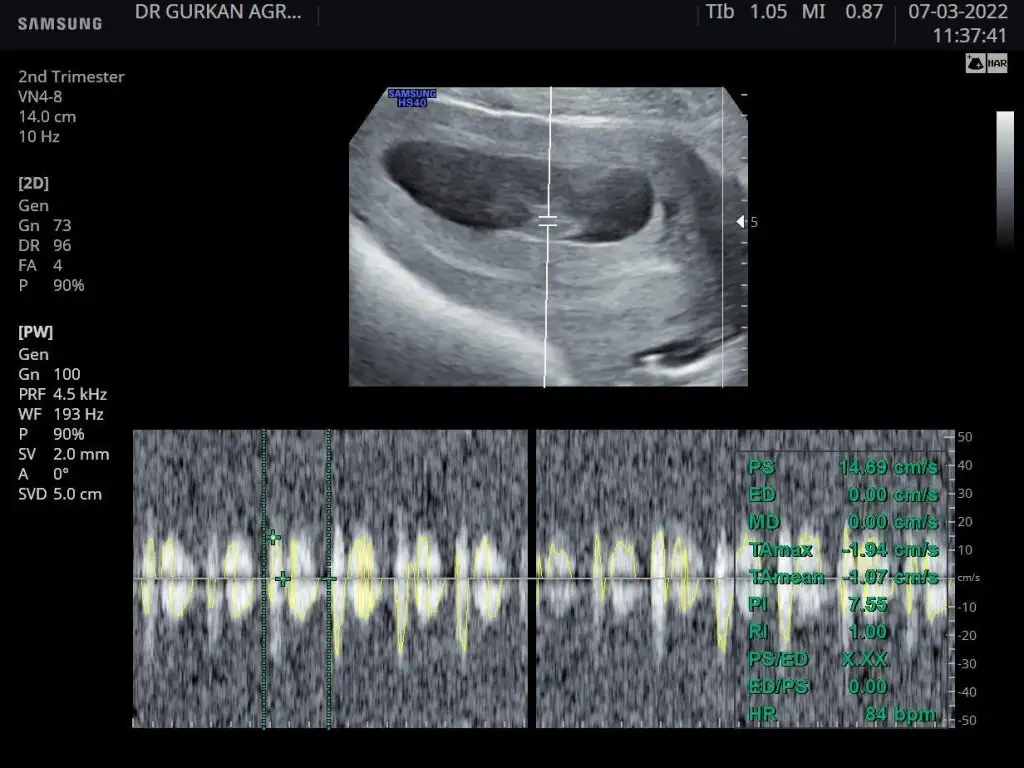

Ikra meyra Ikra meyra merhabalar bize de tahmin yürütür müsünüz ? 3 adet foto var 1. 4 haftalık

2. 6 haftalık

3. 9 haftalık

Kızlar sizceeeeee